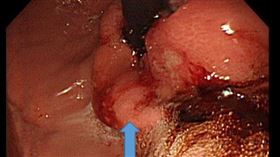

吞嚥卡以為「胃恰酸」就醫診出食道癌

台灣人喜歡熱食的飲食習慣,成了致癌的危險因子!新竹3...

男吃飯「吞不下去」…一檢查竟食道癌

中國泉州一名男子日前發現自己在進食時出現吞嚥困難,且...